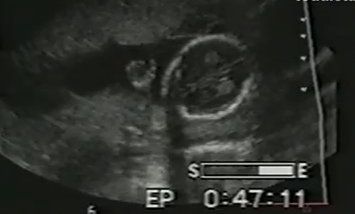

ΑΝΑΠΤΥΞΗ Μέλλουσα μαμά υποστηρίζει πως στο υπερηχογράφημα είδε δίπλα στο παιδί της τον φύλακα άγγελό του!